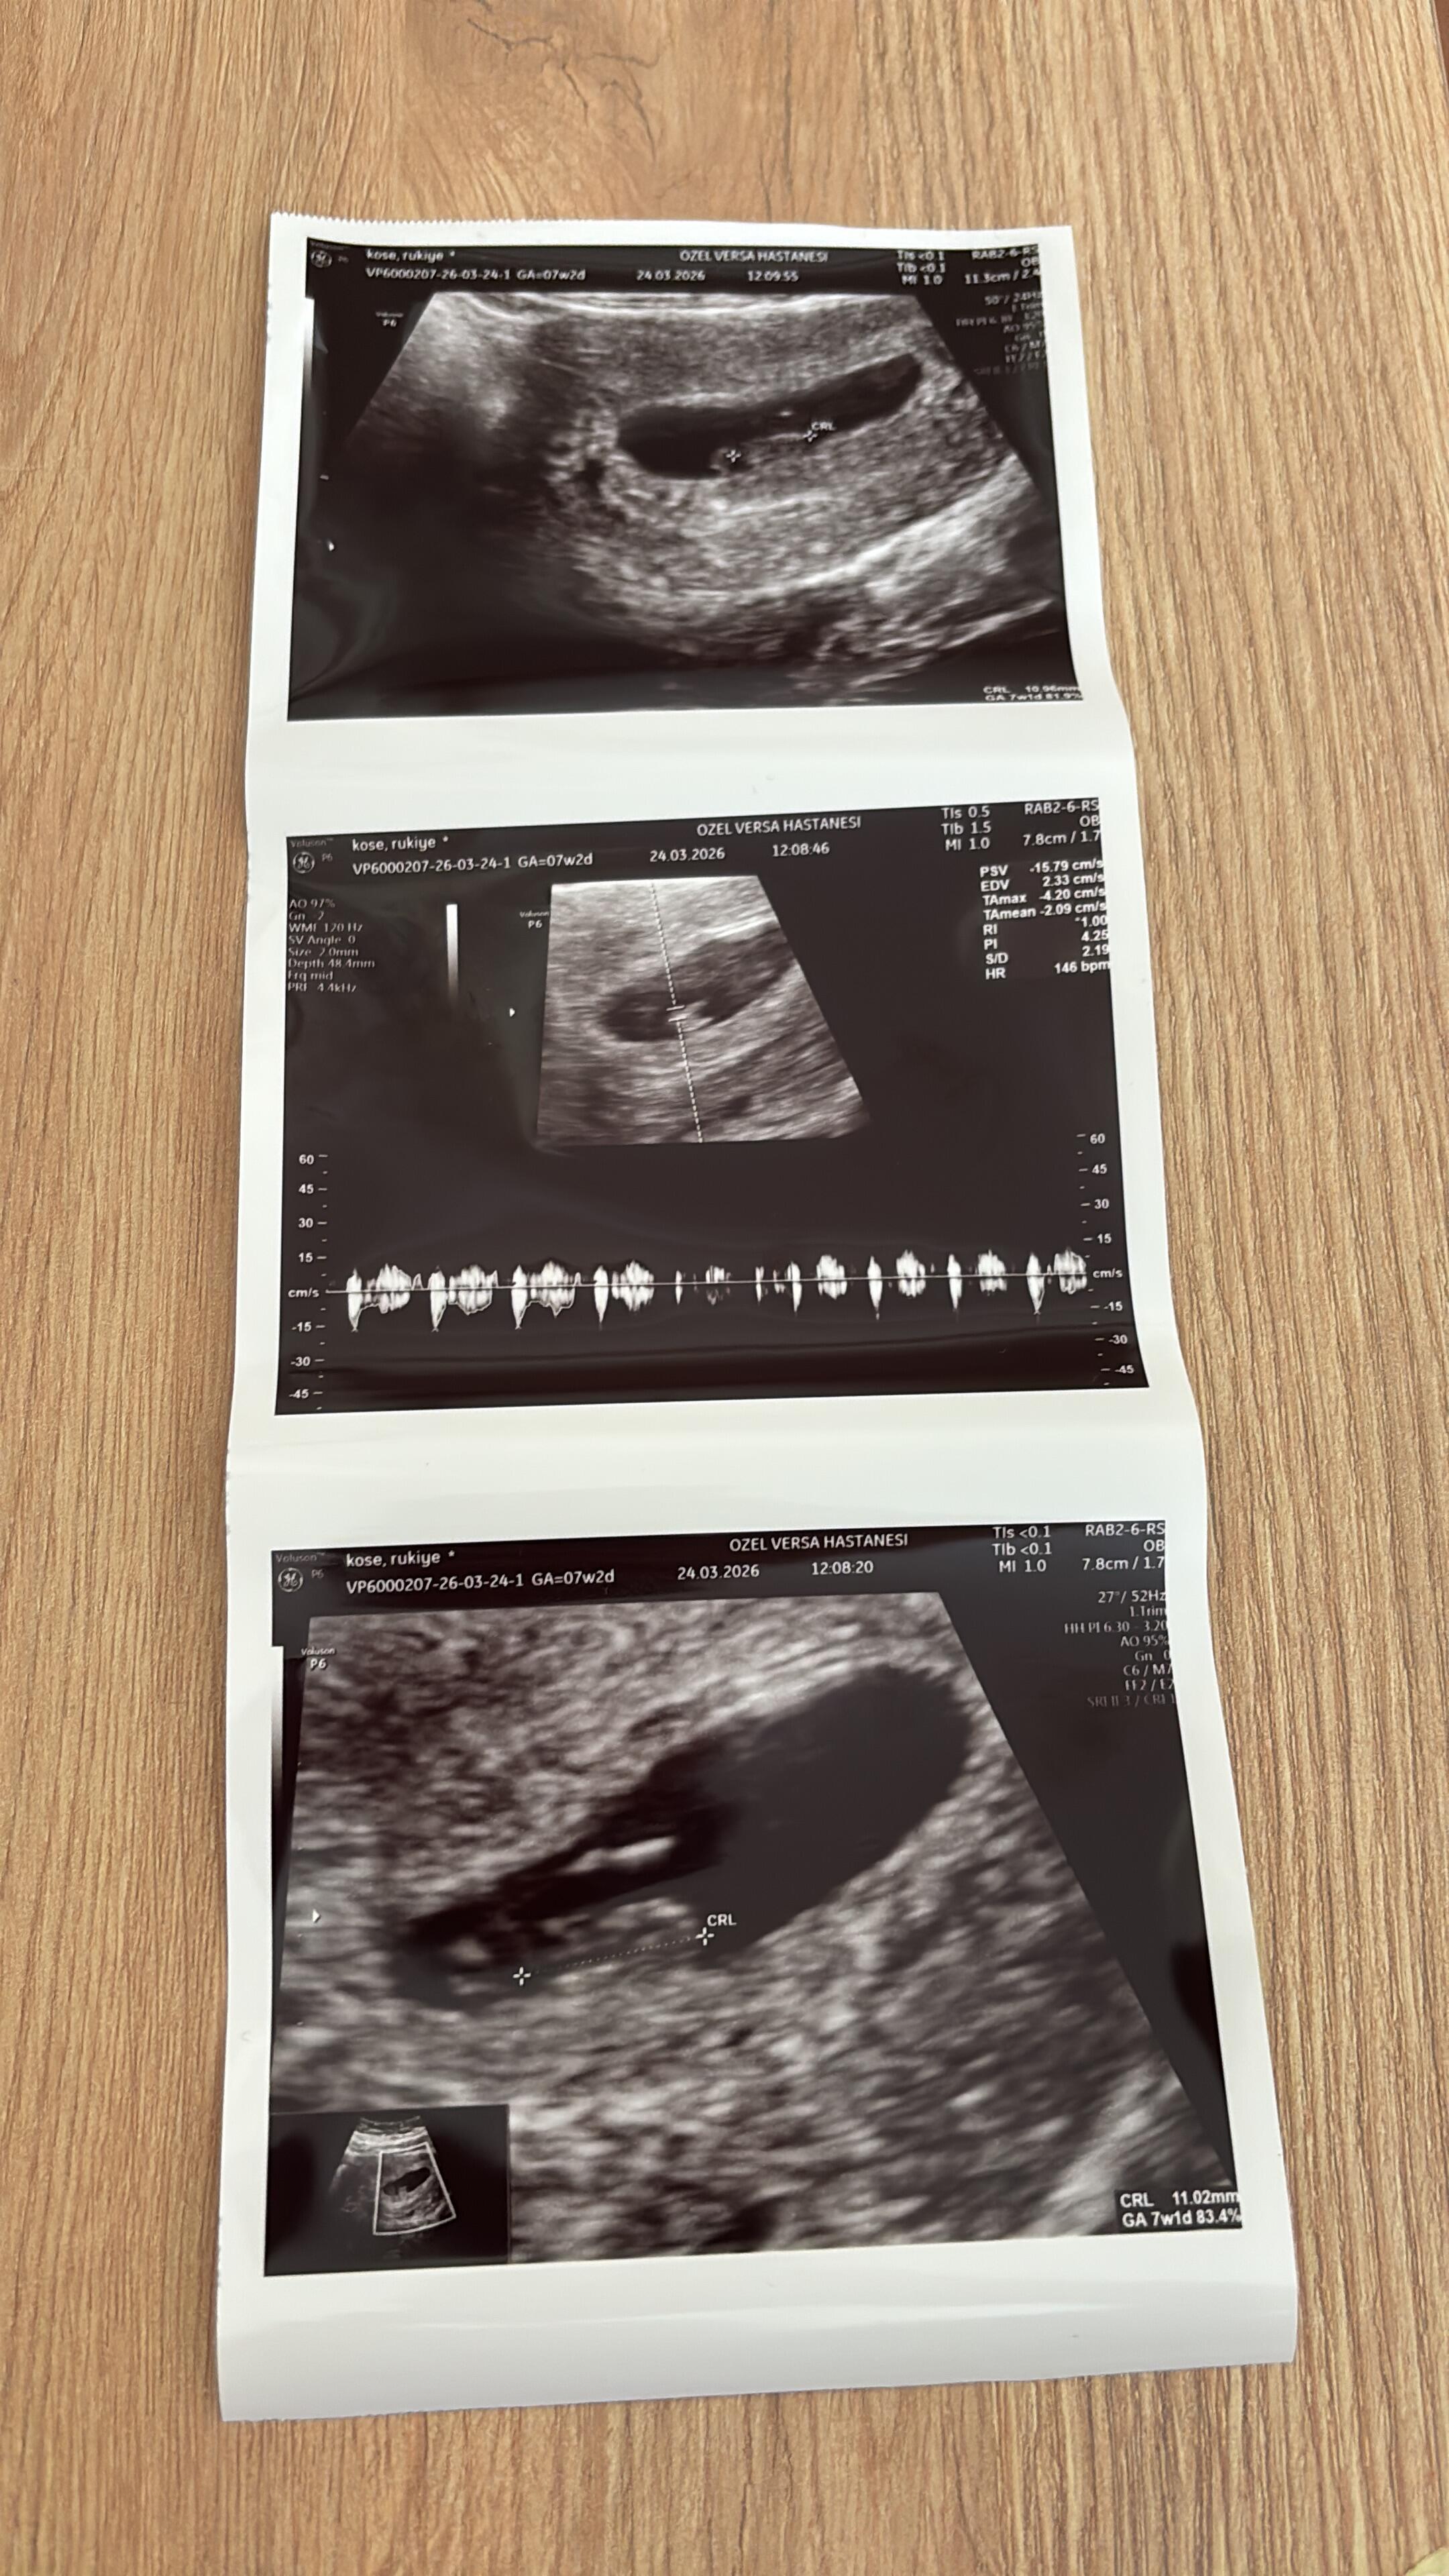

Hep ben tahmin yapıyordum kızlar şimdi ben sizden tahmin bekliyorum Bizim cinsiyetimiz ne teyzeler yorumlarınızı bekliyorum…

Allah nasip ederse inşallah 4. gebeliğim canım